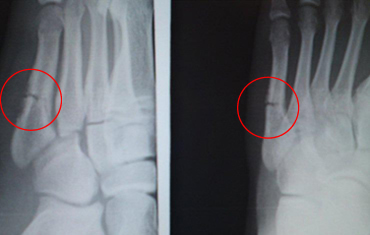

14歳(中学生/バスケットボール選手)男性 症状:中足骨骨折 (酸素カプセル)

回復の経過

酸素カプセル利用経過 2月26日 スタート時

酸素カプセル利用経過 3月19日 初期

酸素カプセル利用経過 4月9日 中期

酸素カプセル利用 4月23日 終了